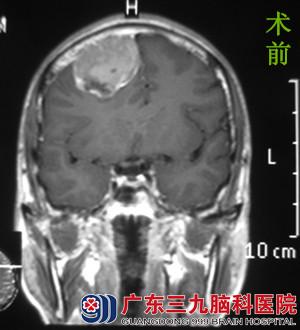

为进一步治疗,阿成一家人来到广东三九脑科医院,经头颅MR检查提示:右侧额部示团块状异常信号影,大小约44.4*48.9*51.7mm,考虑脑膜瘤可能性大。完善相关检查后,由综合神经外科的鲁明主任主刀,在全麻下行右侧额部脑膜瘤切除术。术中见白色肿瘤,质中、包膜完整,予镜下肿瘤全切,手术顺利结束。经专科治疗,患者康复出院。术后病理结果:过渡型脑膜瘤(WHO I级)。